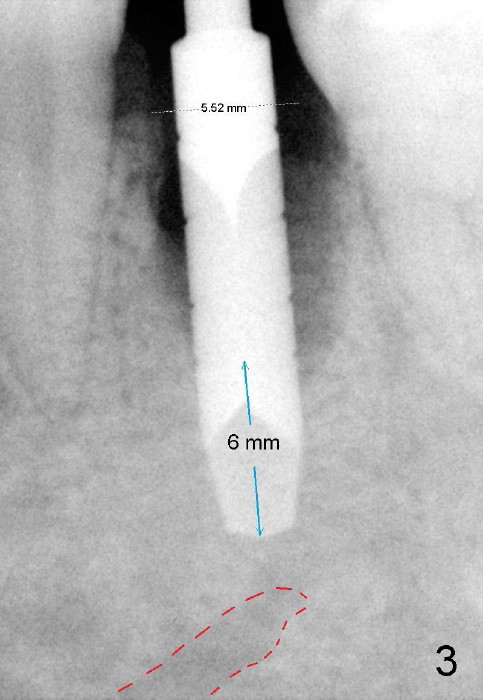

Taking multiple intraop X-ray is also necessary for depth adjustment (Fig.3-5). For example, when a 5x20 mm tap is inserted at the depth of 17 mm, it is close to the mental loop (Fig.4), whereas the binding to the bone is minimal. So a larger implant is to be placed at a shallower depth (Fig.5: 6x17 mm with insertion torque >60 Ncm). The shallower implant placement creates limited space for future abutment and crown (Fig.6,7). A short abutment will be used and the implant margin will be prepared as low as possible. As expected, the wound heals in a week (Fig.8).